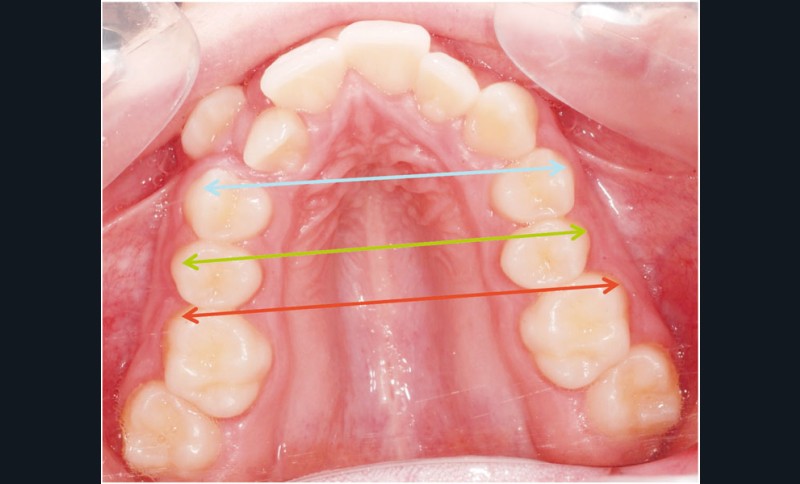

Sans aucun appareillage d’expansion, le maxillaire a été transformé et semble avoir été soumis à une disjonction (fig. 30).

Les moulages avant-après montrent une augmentation du sens transversal de 10 mm au niveau des 1re et 2e prémolaires (fig. 31).